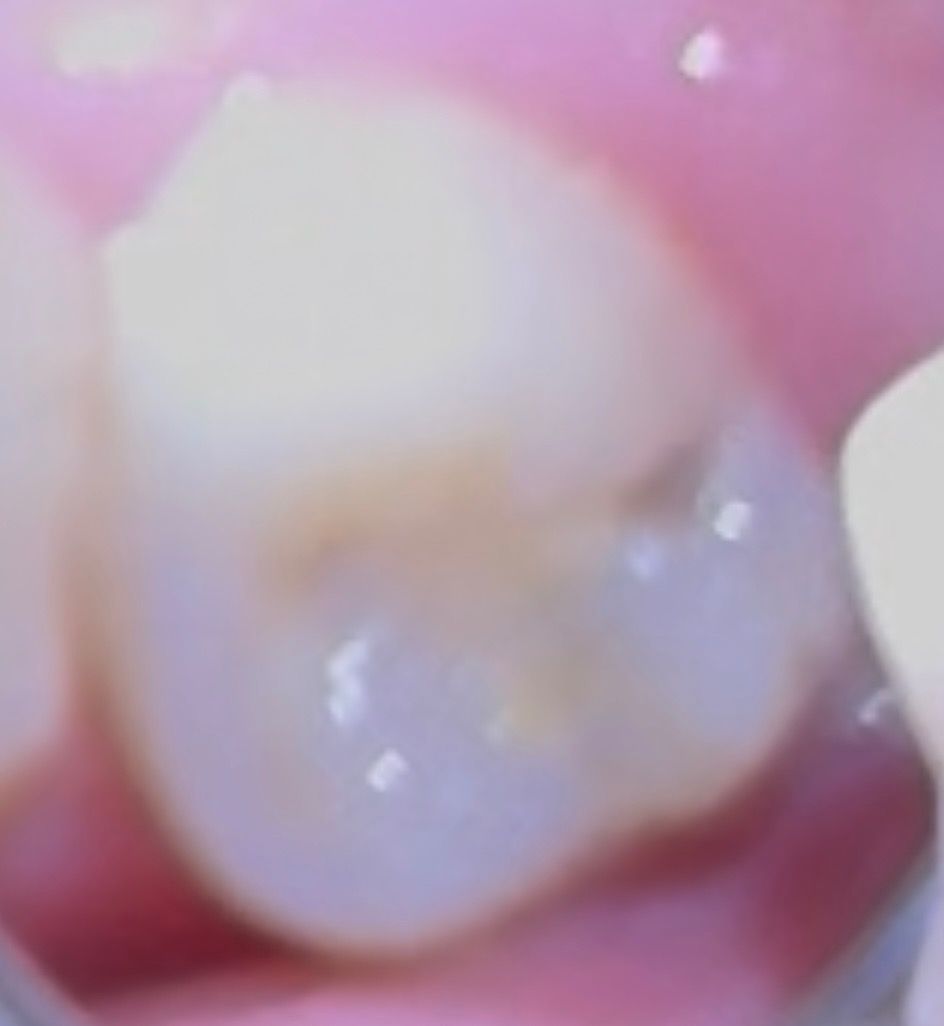

(사진O) 치이의 검은색 부분 충치 혹은 착생중에 무엇잉가요??

먼저, 사진 상에서 맨 뒷부분쪽에 검은 부분이 있습니다

치아 옆부분 즉 주황 동그라미 친 부분에도 검은부분이 있습니다

검은색으로 되어있는 치아 부분에서 충치 발달 가능성이 있을까요?

혹은 착색인가요??

사진에 보이는건 충치가 잇는거 같습니다. 일단 치과에 가셔서 검진을 받아보시는게 좋을것같습니다.

착색보다는 충치 같습니다. 착색은 오히려 충치보다 더 검은 선이 뚜렷합니다. 저건 안쪽 파보면 더 많이 썩어있을 수도 있을 것 같습니다.